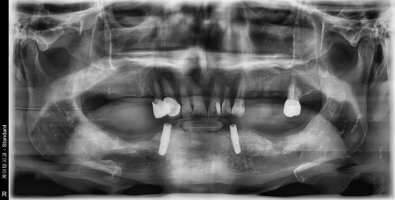

5) 치주질환과 무관한 원인 미상의 치아 흔들림

잇몸에 생긴 암이 치아의 뿌리 쪽으로 자라서 들어가면 치주질환이 없어도 치아가 흔들리는 증상이 생길 수 있습니다. 치아가 흔들리는 증상 외에도 이를 빼고 2주 이상 아물지 않는 경우에도 추가적인 검진이 필요합니다.